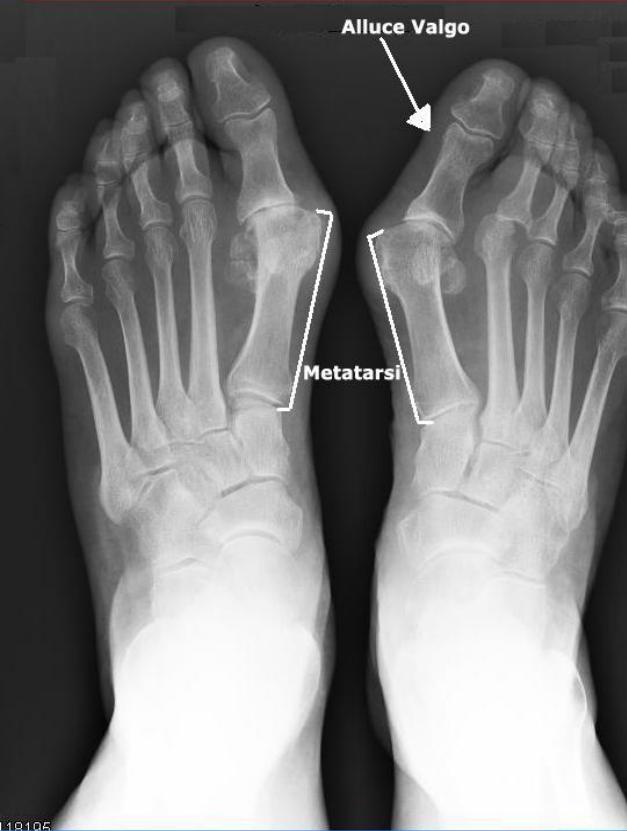

Quali sono i vantaggi delle terapie mini-invasive per le malattie del piede? A spiegarci la loro applicazione è il dottor Guido Carbone (contattabile al 393.3278751 o al 335.6635217), medico chirurgo ortopedico specializzato in queste innovative pratiche. Sì, perché per alluce valgo, dito a martello e per le più diffuse metatarsalgie i metodi conservativi non bastano più: possono essere curati con successo grazie a nuove metodiche. Il dottor Carbone lavora alla clinica Sant’Anna di Brescia e ha scelto dedicare particolare impegno e attenzione alle problematiche del piede e dell’avanpiede. Maggiori informazioni sono disponibili sul sito del Dottor Carbone.

«Per la cura dell’alluce valgo queste tecniche sono straordinariamente efficaci, ma ci sono anche tante altre patologie dell’avanpiede che possono essere risolte attraverso di esse. Il chirurgo però deciderà volta per volta, perché le tecniche mini-invasive possono essere utilizzate con profitto solo in situazioni selezionate. Tra le altre patologie su cui questi metodi operativi sono efficaci ci sono le dita a martello e le metatarsalgie più ricorrenti».